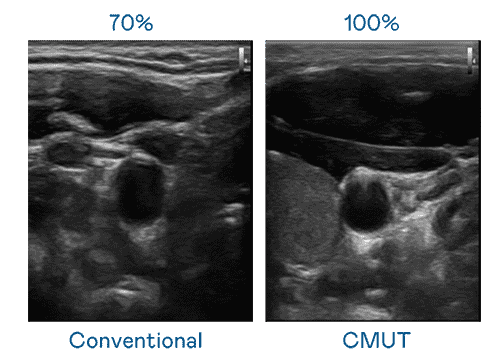

CMUT 技术是一种用电容式微机电元件来产生超音波讯号的技术。。。。与传统 PZT 压电式技术相比,,,CMUT 频宽增加 30%,,更宽频的超音波讯号让影像解析度大幅提升,,,,是实现高影像品质医疗超音波扫描、、、、促进精准医疗发展的关键技术。。。。

大频宽带来超清晰影像

超音波影像的解析度高低,,首先取决于探头能发出的讯号频宽。。。糖果派对 CMUT 可提供高清晰的超音波讯号,,提供高频宽、、、、高灵敏度、、、、影像纹理细节更高的超音波影像,,,,协助医护人员缩短影像判读时间及利用精准的医疗影像进行诊断。。